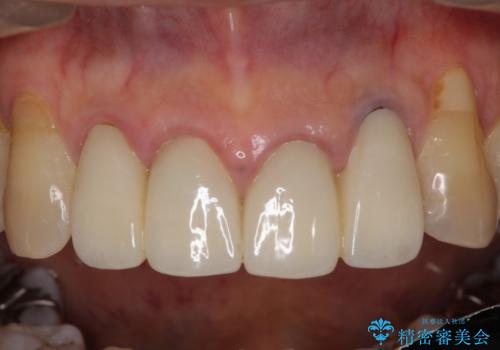

- 昨年治療した前歯の根尖部に痛みを感じ、ラバーダムや顕微鏡を用いた根管治療を希望されて、転院された患者様です。

前医にて神経を取り除いた処置を行った際、ラバーダムが使用されなかったとのことで転院されてきました。

根管治療を実施した後、オールセラミッククラウンに補綴することとしました。

前歯のセラミッククラウンを装着したばかりであったので、根管治療のためにクラウンを壊さなければならないことを残念に思っていらっしゃいました。

しかし、根管治療後はすぐに痛みがひき、治療を受けられて良かったとのことでした。